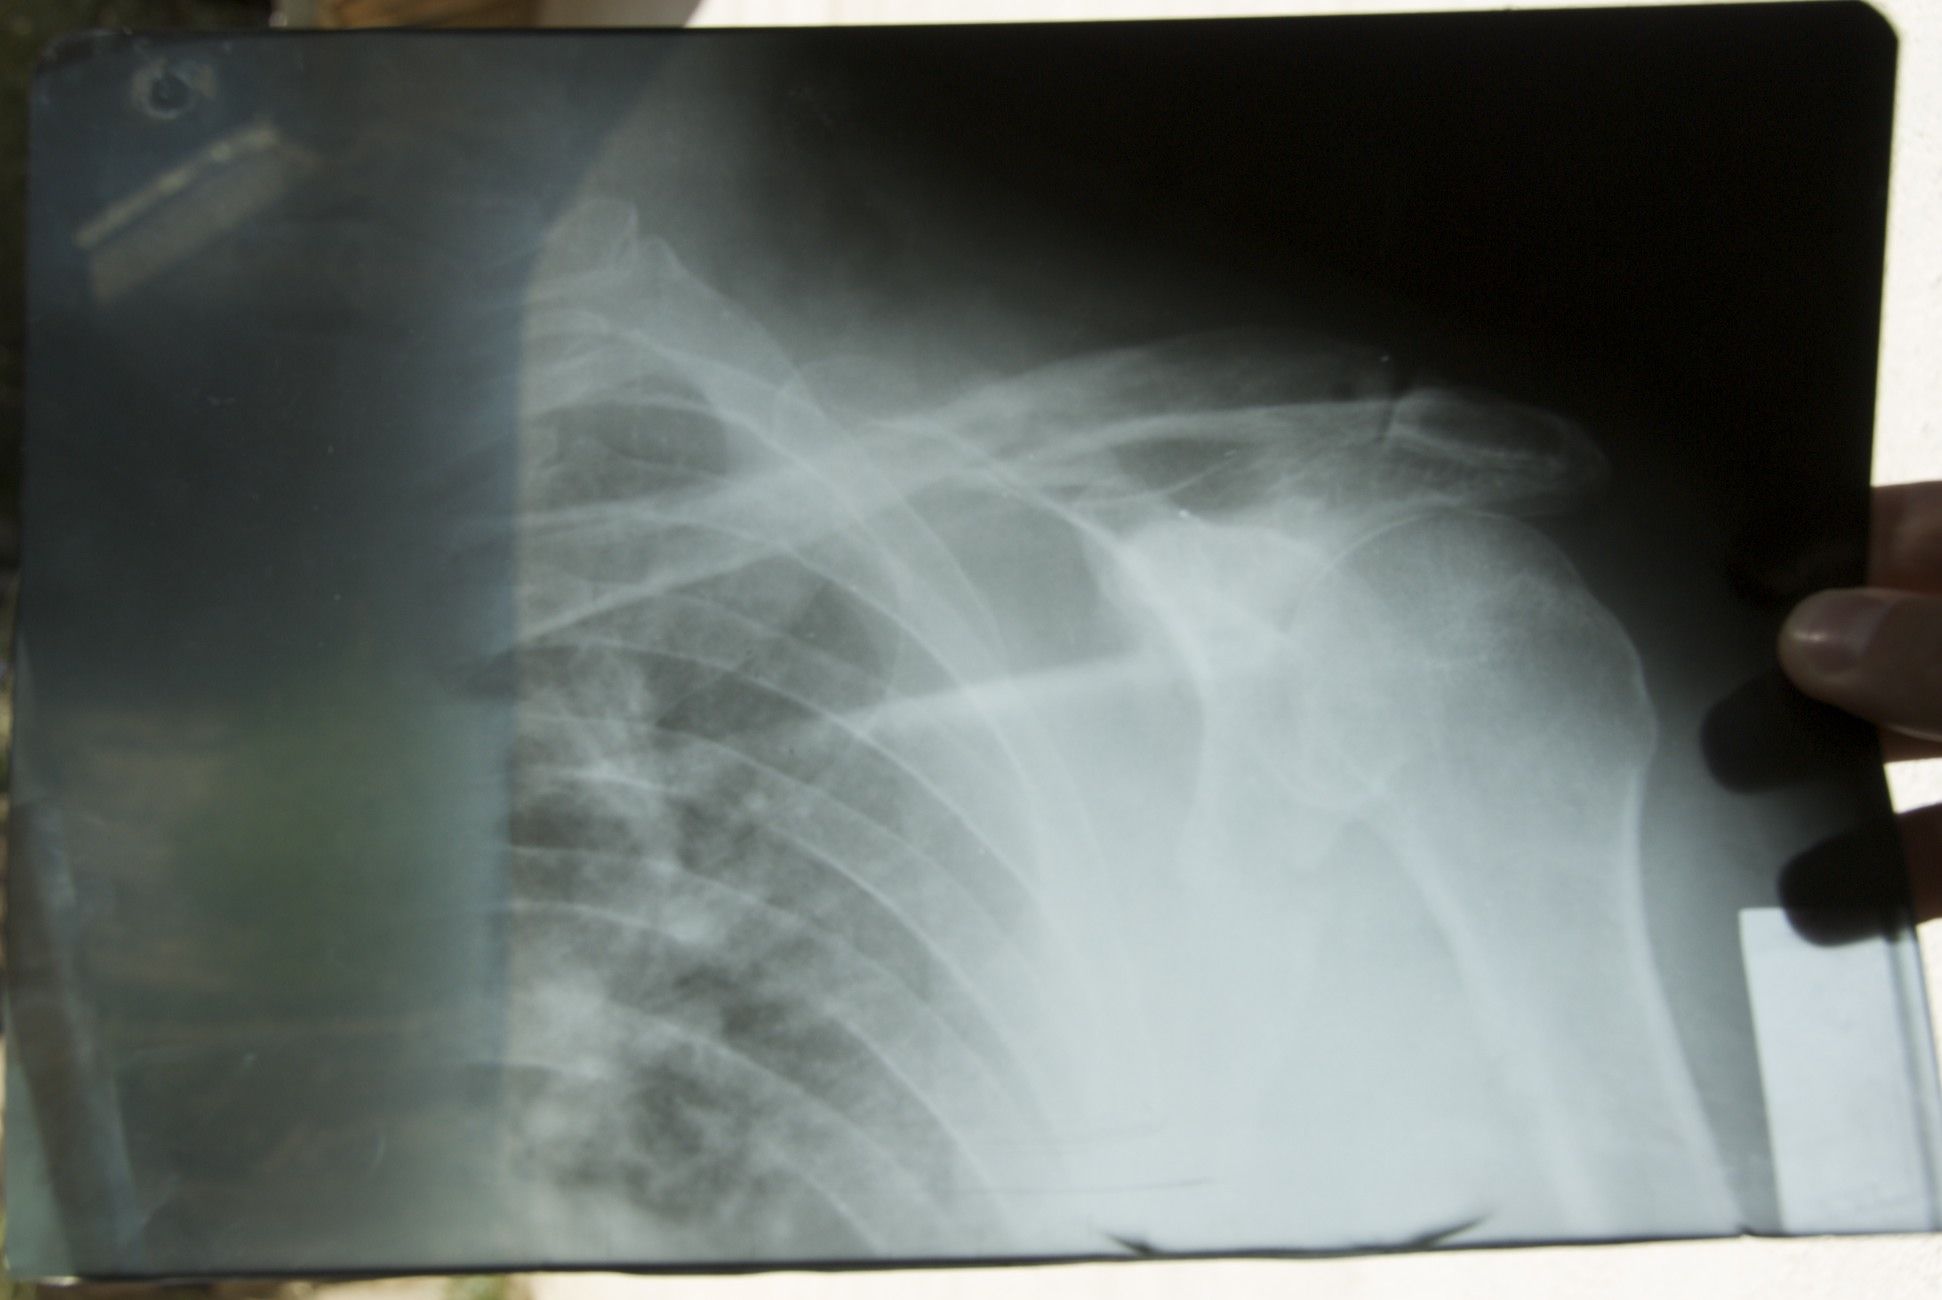

První rentgen z Chorogu - kobaltová lampa

Zkusil jsem se opřít o pravou (zdravou ruku), nic - neměl jsem vůbec sílu se o ní opřít, povolila, a já se svalil na zem, ta bolest byla příšerná, jen jsem zoufale syčel, slzy na krajíčku... "Ty vole", říkal jsem si: "Tys to posral".... Ležím na pravým neobouchaným boku, ale levá strana je jak v ohni. Nikdy bych nevěřil, že pitomá klíční kost tohle udělá. (Až doma se přišlo na to, že byla zlomená lopatka, čtyři žebra, roztříštěný loket a štíplá pánev)

Kluci vyrážejí "do města chlastat", já zůstávám sám, zase chvilku. Konvicí čaje se smardlavejma cigárama, doutník už jsem neměl víc jak měsíc. Čekám až budu tak utahanej, že snad usnu. Je to den po nehodě, jsem celej rozlámanej. Jak jsem sebou v noci mlel, tak ty zlomený kosti jsou zas přes sebe, stejně jako než mě zafačovali... dobře tak 3 - 5 cm, rameno mi visí divně dolů, na boku se mi začíná dělat obrovská tvrdá boule... obrovská to nepřeháním, odhadem tak kolem jednoho až dvou kil hovězího na objem... loket jak bambuli... udělal jsem si z hadru jen takový závěs na ruku, aby se mi neplandala kolem toho bolavýho boku. Každej nádech, každej pohyb svírá hrudník...